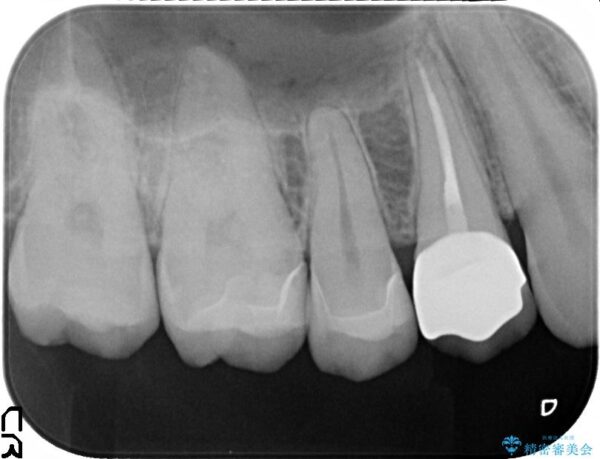

治療前

銀歯を除去してのセラミック治療[ メタルフリー ] 治療前画像 銀歯を除去してのセラミック治療[ メタルフリー ] 治療前画像 銀歯を除去してのセラミック治療[ メタルフリー ] 治療前画像